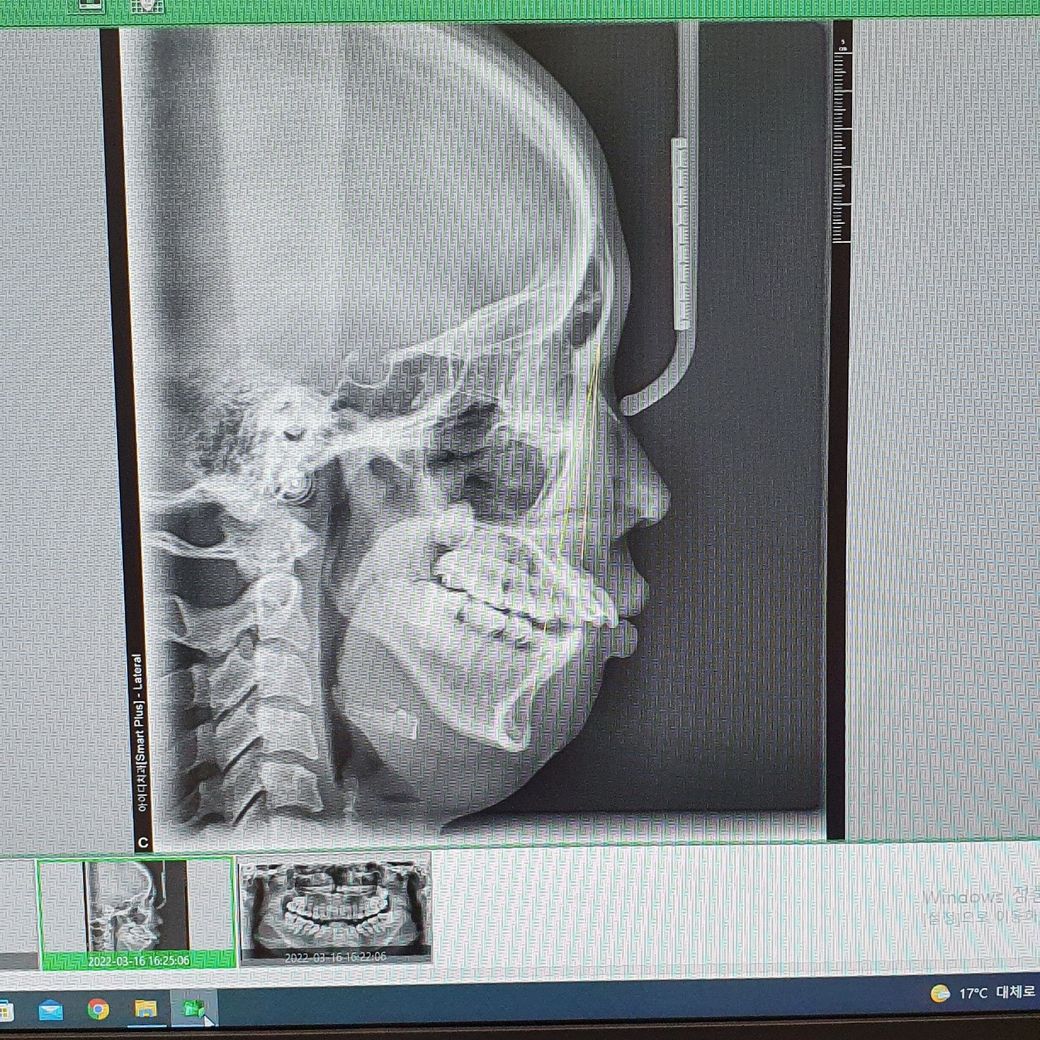

제가 무슨 퇴행성 턱관절염이 있다고 교정할거면 양악도 해야된다 하셨어요

골격적으로 인한 부정교합이라면 교정만으로는 해결이 어렵기 떄문에 수술과 병행을 하셔야될수도 잇습니다.

현재 아래 사랑니 발치까지하고 술전교정을 본격적으로 들어가진 않은것 같습니다 수술이 포함된 치료와 포함되지 않은 단순 교정치료는 결과도 다르고 치료 과정도 다릅니다 빨리 마음이 바뀌었음을 치과의사에게 알리는 것이 좋습니다